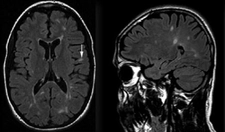

Kafa içindeki lezyonlar, çeşitli nedenlerle oluşabilen anormal doku büyümeleri veya hasarlarıdır. Bu lezyonlar, beyin dokusunda, meninkslerde veya kafatasının diğer bölgelerinde gelişebilir. Lezyonların varlığı, çeşitli belirtilerle kendini gösterebilir ve bu belirtiler, lezyonun türüne, boyutuna ve bulunduğu yere bağlı olarak değişiklik gösterebilir. Lezyon TürleriKafa içindeki lezyonlar, genel olarak birkaç ana kategoriye ayrılabilir:

Tanı YöntemleriKafa içindeki lezyonların tanısı, genellikle hem klinik muayene hem de görüntüleme yöntemleri ile konulur. Kullanılan başlıca yöntemler şunlardır: